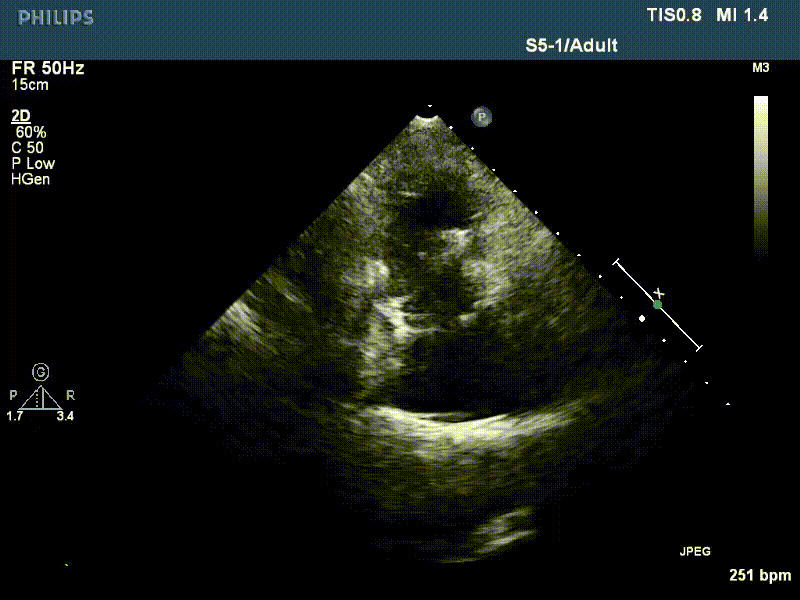

流并分別伴有房顫和房撲,高外科手術風險。術前超聲提示,兩例患者下腔靜脈寬度分別為13mm和29mm,右房內徑(上下徑和左右徑)分別為52×41mm和53×43mm,彩色多普勒顯示極重度三尖瓣反流,VCW分別為14×15mm和10mm。

1年前,兩例患者因難治性雙下肢水腫輾轉多家醫院尋求救治,考慮到兩例患者高齡、基礎疾病多、STS評分高,不適合傳統外科開胸手術,葛均波院士及其團隊周達新教授、潘文志教授、張源博士、陳莎莎博士、陳丹丹博士聯合心外科王春生、魏來主任,麻醉科繆長虹、郭克芳主任以及心超室的潘翠珍教授、李偉教授共同討論決定,采用我國創新器械LuX-Valve Plus經血管三尖瓣置換系統為患者進行手術。相較于第一代產品LuX-Valve,LuX-Valve Plus經血管三尖瓣置換系統對輸送系統進行了全面升級,實現了經頸靜脈入路的方式,進一步減小了手術風險和對患者的創傷。目前隨訪1年心超結果顯示,三尖瓣極重度反流消失,人工三尖瓣瓣膜穩定牢固,瓣葉活動度良好,右心室及下腔靜脈明顯縮小,心輸出量增加。兩位老人手術后沒有出現過胸悶氣促的癥狀,下肢水腫緩解,活動耐力提升,生活質量也大為提高。